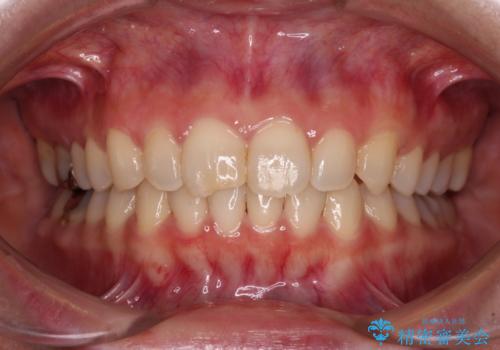

- 前歯のデコボコと八重歯、開咬を気にして来院された患者様です。

骨格的に下顎骨が上顎骨に対して後退位であったため、上顎の左右第一小臼歯を抜歯し、デコボコを改善するとともに開咬を改善していくこととしました。

舌の突出癖により開咬となっていたため、突出癖改善のためのトレーニングをしっかりと行っていただき、予定の期間で無事に治療を終えることができました。